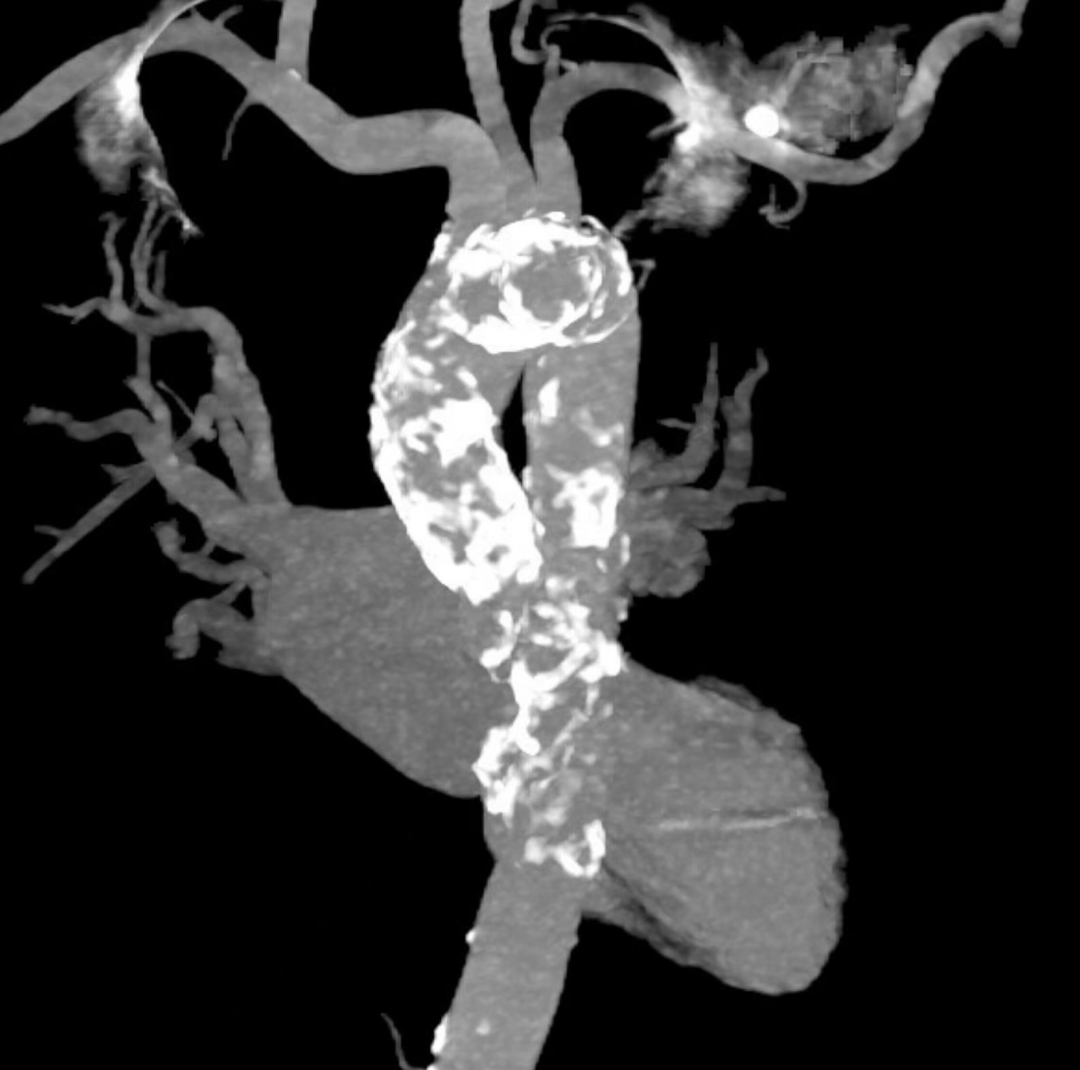

心脏结构方面经过详细的术前评估,结果发现老太太不仅主动脉瓣重度狭窄合并中度关闭不全,而且右冠状动脉中段管腔发生多发95~99%狭窄,还合并有很罕见的“瓷化主动脉”。所谓瓷化主动脉是指升主动脉弥漫性钙化,主动脉呈蛋壳状外观,通俗讲主动脉就像瓷器一样脆弱。除了瓷化主动脉,主动脉瓣严重钙化,同时钙化还向下延伸到左室流出道及二尖瓣根部,进一步加大操控的难度,增加并发症发生的风险。心腔扩大,心尖部可见局部心肌薄弱,在操作过程容易发生心肌穿孔破裂。评估结果提示患者手术风险极高,手术难度极大。

术后影像图

术前影像图